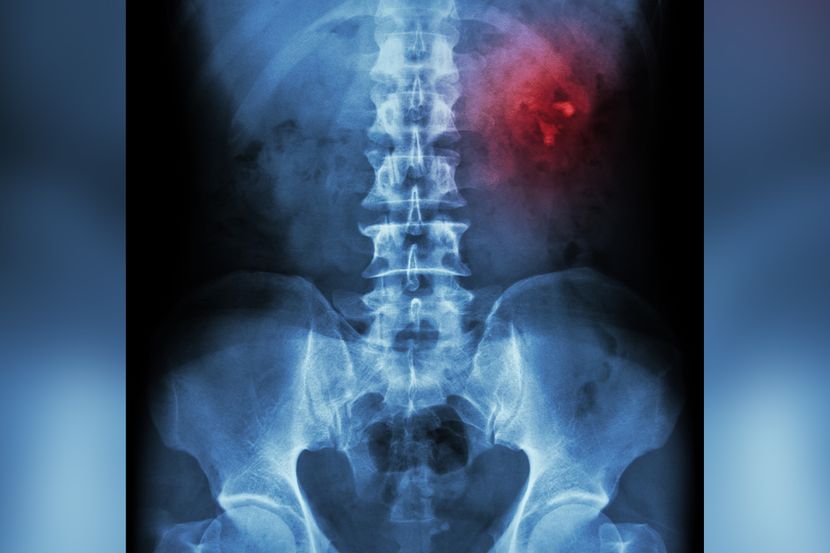

Kamen u bubregu (nefrolitijaza) je tvrda naslaga minerala i soli koja nastaje u bubrezima. Lekari kažu da je ova bolest u bitnoj meri posledica loših životnih navika, pre svega nedovoljnog unosa vode. Primećuje se da pacijenti sa kamenom u bubregu često zaborave da piju vodu. Ne možemo u potpunosti da kontrolišemo sve faktore rizika jer je nefrolitijaza uslovljena i genetikom ili određenim zdravstvenim stanjima. Kada govore o rizicima koje možemo da kontrolišemo, stručnjaci pre svega navode dovoljan unos vode, ali i svakodnevni stres koji može, kako izgleda, polako ali sigurno da deluje na svaki deo tela pa i na bubrege.

Kamenčići u bubrezima ili mokraćnim putevima posledica su smanjene zapremine urina i skupljanja kalcijuma i drugih supstanci koje čine kamen. Dehidratacija, to jest smanjen unos tečnosti, najčešći je faktor rizika za pojavu kamena u bubregu.

Dr Sangeetha Murugapandian, specijalista za bolesti bubrega, kaže da kamenčići u bubrezima mogu da budu veličine „zrna peska“ i da tada prođu kroz urinarni sistem bez bilo kakvih problema. Međutim, često su kamenčići dovoljno veliki da blokiraju mokraćne puteve i dovedu do izrazito jakog bola u leđima ili sa jedne strane tela, pojave krvi u urinu, učestalog mokrenja i mučnine.

Savet je da odmah potražimo pomoć ako dođe do jakog bola u donjem delu leđa, sa strane ili u stomaku. Alarmantni su znaci i simptomi kao što su krv u mokraći, otežano mokrenje, bol pri mokrenju ili česta potreba za mokrenjem, mučnina i povraćanje. Bitno je da se kamen u bubregu otkrije na vreme kako ne bi došlo do komplikacija, kao što su blokada protoka urina (hidronefroza), ozbiljne infekcije mokraćnih puteva, a na kraju i oštećenje tkiva bubrega.